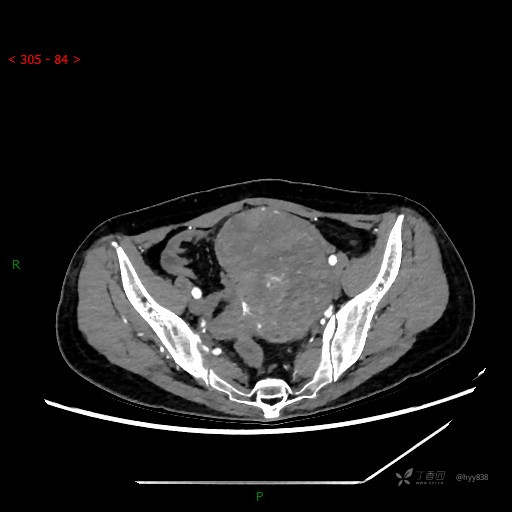

盆腔CT平扫